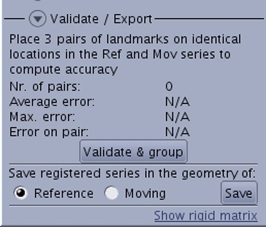

| Quality Check Tools

| Use to check the accuracy of registration, (Fused, Inverse, Tiles and Window views). |

| Link Planes

| Use to display all views either in the Reference or the Registered (i.e., moving) series’ plane. Reference is activated by default. |